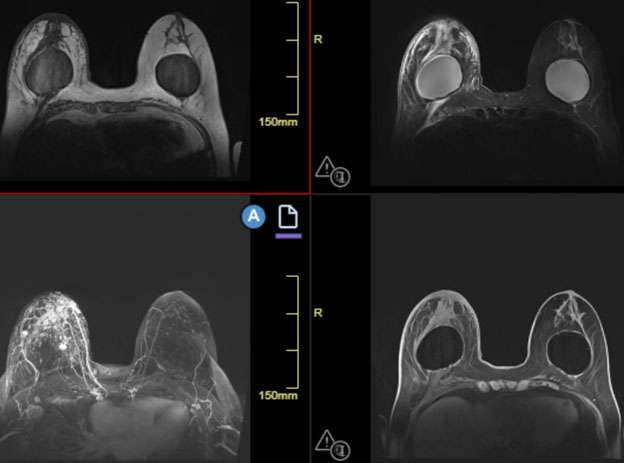

When MRI is performed, findings may include a heterogeneously enhancing mass and skin thickening. MRI is the most accurate imaging technique in detecting primary breast parenchymal lesions in cases of inflammatory breast cancer and may assist in delineation of disease extent (Figure 2).

WU: Skin Change Figure 2

Figure 2. Dynamic contrast enhanced MRI was performed for evaluation of extent of metastatic disease in a 74-year-old female with skin biopsy confirmed right-sided inflammatory breast cancer. In a clockwise fashion, the images included are a pre-contrast T1, STIR, first pass post-contrast, and MIP images. Most notable are extensive enhancing masses and nonmass enhancement involving most of the right breast, with involvement of the overlying skin and nipple areolar complex. Additionally, there are multiple enlarged level 1-3 axillary lymph nodes partially imaged on the MIP sequence.